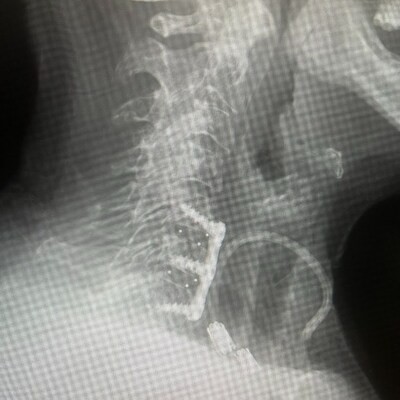

CREDIT: ZAVATION MEDICAL PRODUCTS

Zavation Medical Products, LLC announces the release of its most advanced cervical interbody implant to date – the integration of NanoPrime Titanium Ion Bond Technology with the company's proprietary Labyrinth porous PEEK architecture. This combination is engineered to elevate the mechanical advantages of PEEK with the biological benefits of titanium.

Combined, these technologies deliver an implant platform that maintains the imaging clarity and elastic modulus of PEEK while introducing an osteoconductive nano-surface intended to promote early cell attachment, induce hydrophilic wicking, and reduce stress shielding.